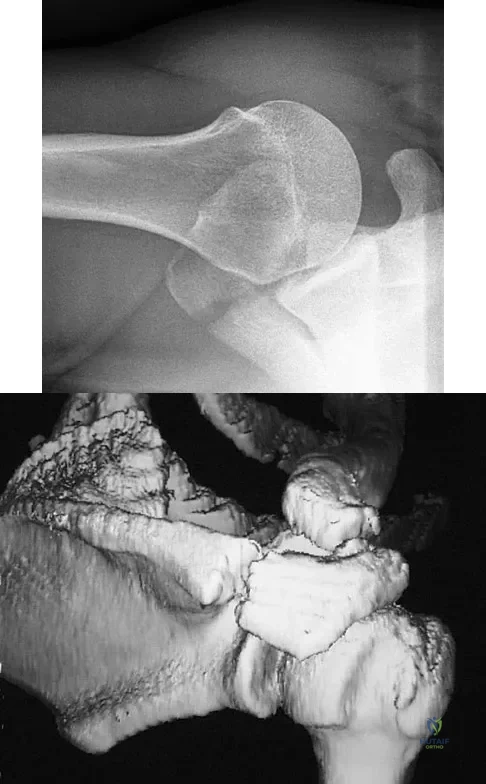

A 22-year-old right hand-dominant man who fell off his motorcycle onto the tip of his right shoulder 2 weeks ago now reports pain and difficulty raising his right arm. Examination reveals tenderness and gross movement over the lateral scapular spine and severe weakness during resisted abduction. A radiograph and 3D-CT scan are shown in Figures 24a and 24b. What is the next most appropriate step in management?